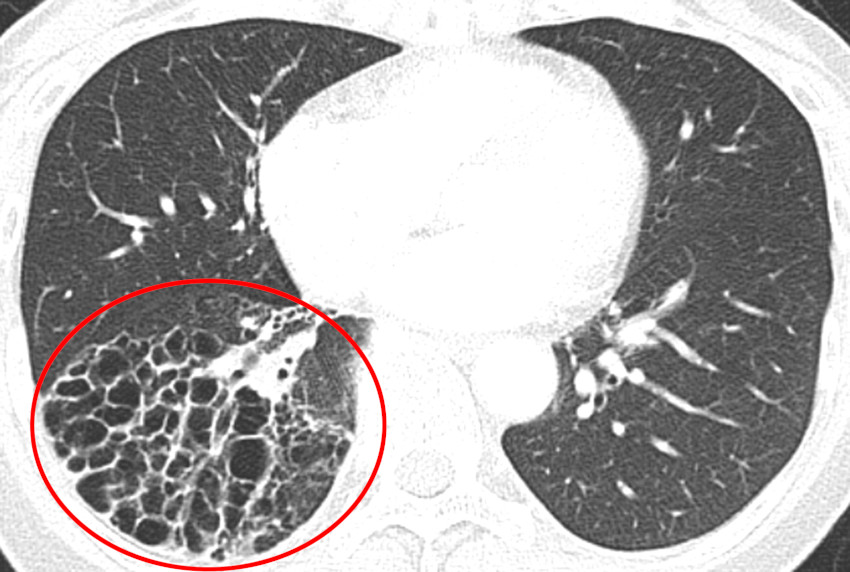

Bronchiectasia

- Descrizione: Dilatazione anormale di uno o vari bronchi. Produce Alitosi, attacchi di Tosse e mucosità purulenta.